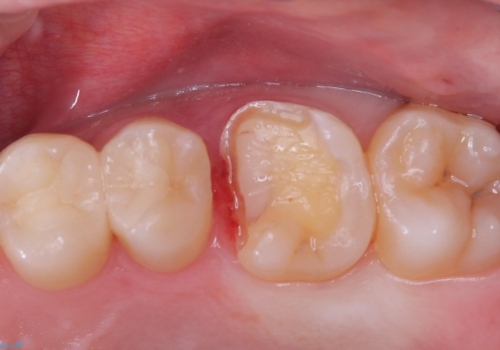

- 主訴:右上6番目の歯が黒ずんで見える。

右上6番に保険適用の歯冠色材料を使ったインレーが入っていましたが、歯質とインレーとの境目に不適部位が存在しそこから二次う蝕になっていました。

セラミックインレーでのやり替えを提案し、また残存歯質量と破折のリスクを説明し、アンレー形態となりました。

おそらくCAD/CAMインレーと思われる補綴物と歯質の不適合による二次う蝕でした。また、インレーを除去したところ、側室底面の歯質の上に裏層材が一部乗っており、歯質マージンとなっていなかったこともリークの一つの原因と考えられます。

適合性、審美性、材料安定性からセラミックインレーでのやり替えとなりました。う蝕を除去いていくと、残存歯質が薄く破折リスクの高い部位が出てきたため患者さんにも説明し、アンレー窩洞としました。